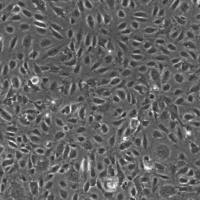

人脑血管外膜成纤维细胞产品描述:

成纤维细胞是来源于胚胎中胚层间充质细胞。他们已经广泛用于广泛的细胞和分子研究。有充分的证据表明,成纤维细胞在身体的不同部位是本质上不同的[1]。血管外膜被定义为最外层血管的结缔组织。血管成纤维细胞的功能紊乱是发病的机制之一。增生性反应可导致观察到的外膜增厚在氧诱导肺动脉血压升高。

ScienCell研究实验室成功提取出人脑血管外膜成纤维细胞。每个瓶包含> 5×10 ^ 5细胞1毫升容量。经检测该细胞未受到乙肝病毒、丙肝病毒、支原体、细菌、酵母和真菌感染。ScienCell研究实验室提供的HBVAF保证进一步扩大15倍增长。配套培养基:推荐使用纤维细胞培养基(Cat.No.2301)。产品使用说明:仅供研究使用!